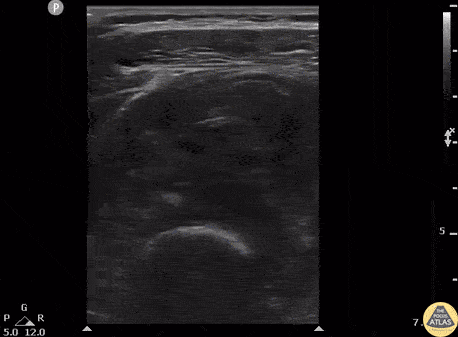

Patient presents to the ED with severe thigh pain following a subacute MMA injury. After proximal DVT was ruled out, POCUS revealed hypoechoic oval masses in the vastus intermedius and peripheral calcifications with shadowing adjacent to the femur. Image courtesy of Robert Jones DO, FACEP @RJonesSonoEM Director, Emergency Ultrasound; MetroHealth Medical Center; Professor, Case Western Reserve Medical School, Cleveland, OH View his original post here